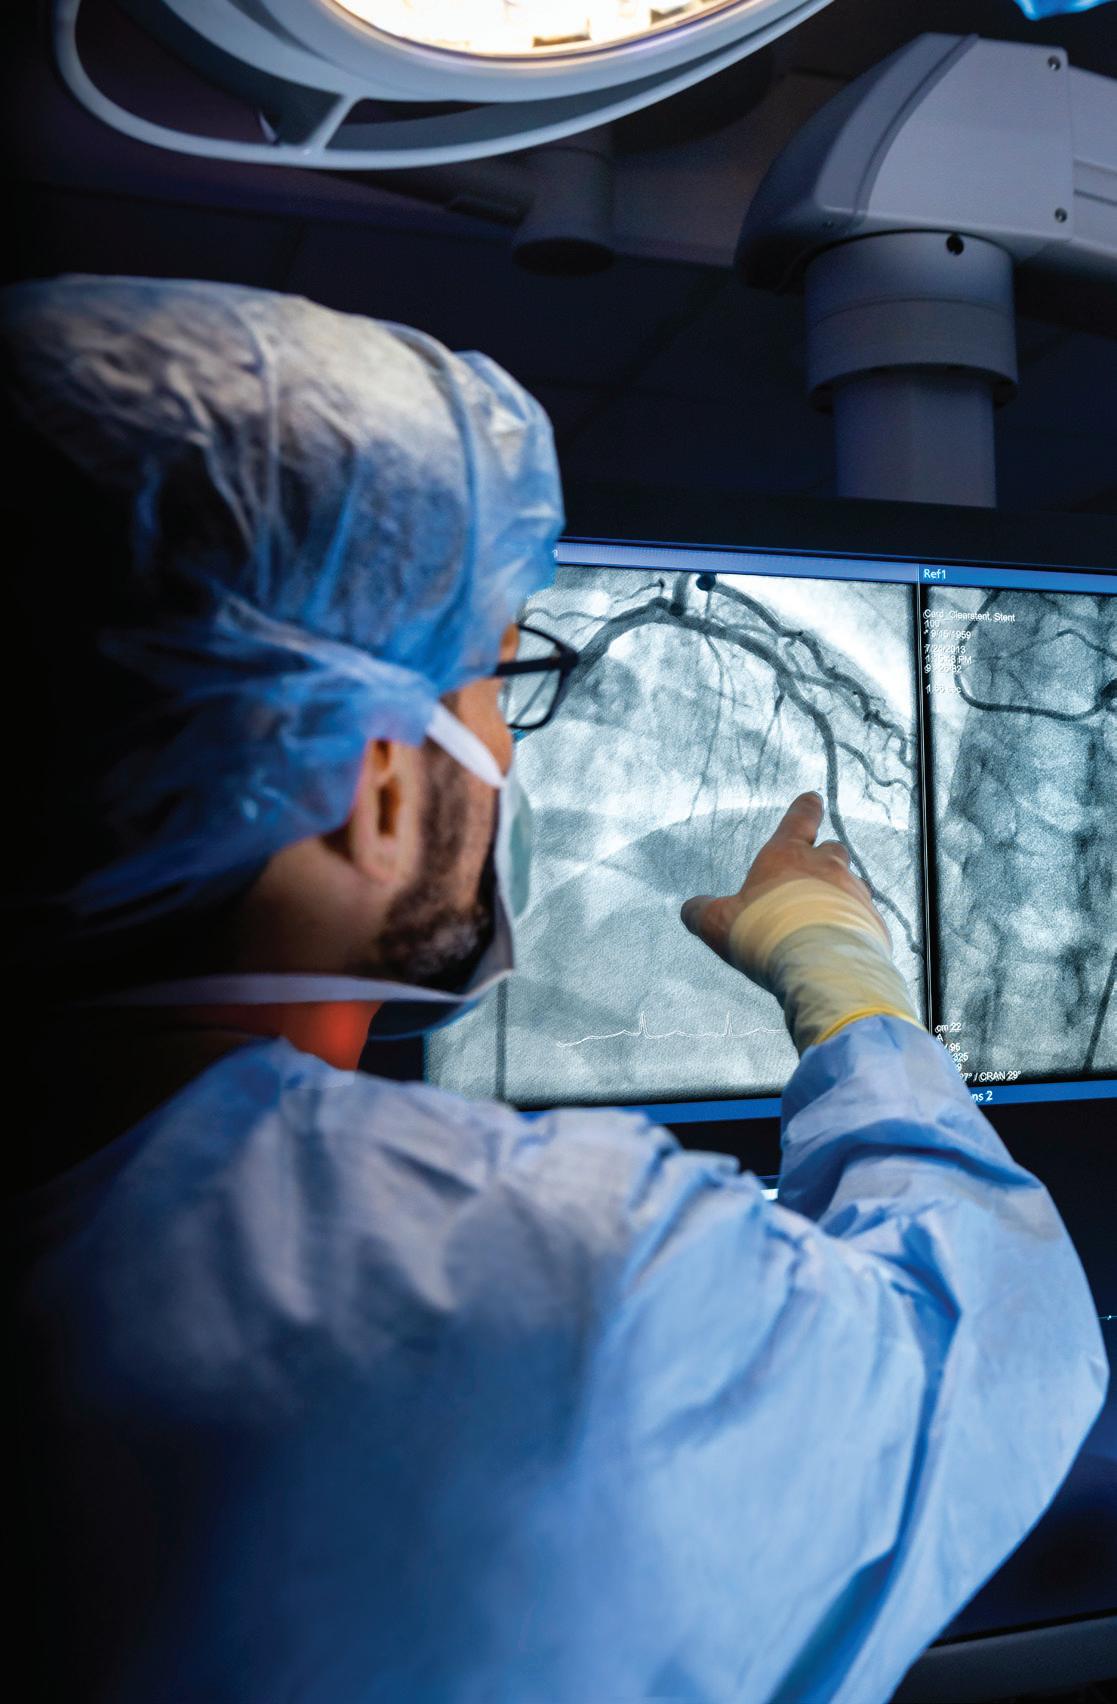

The brightest minds and biggest hearts in cardiac and vascular care

Keeping your heart healthy means everything. At Nuvance Health Heart & Vascular Institute, the nation’s top talent and experienced care teams offer innovative treatments, utilize leading technology, and provide care centered around you. So you can put your whole heart into the moments that matter most. Book an appointment with a heart & vascular specialist at nuvancehealth.org/hearthealth